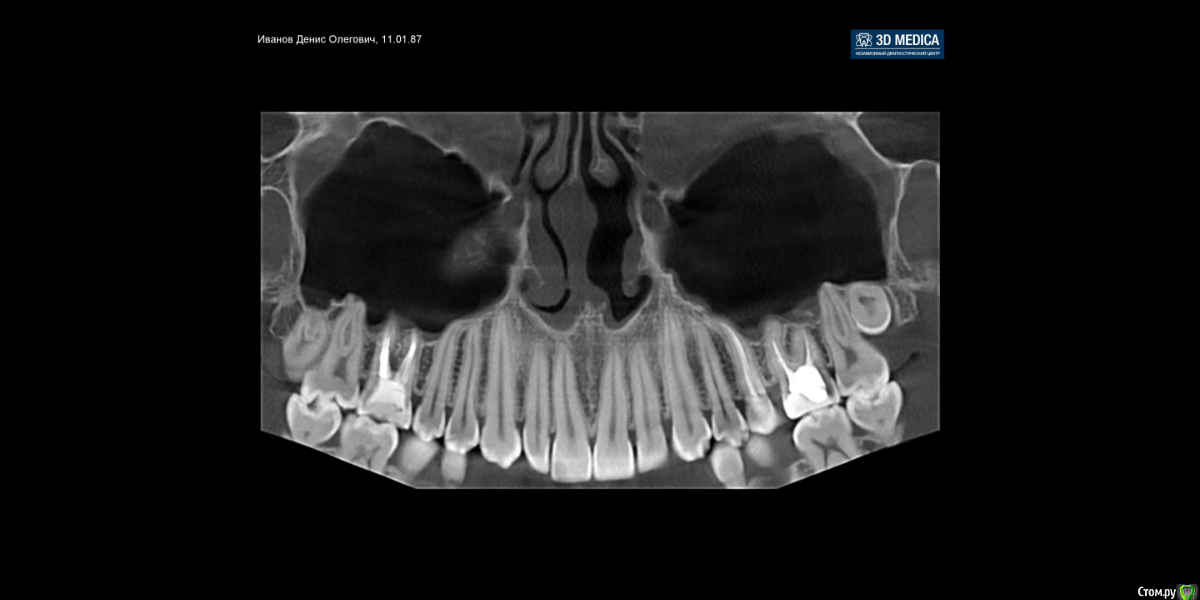

Dench Опубликовано 6 февраля, 2017 Поделиться Опубликовано 6 февраля, 2017 (изменено) Добрый день, уважаемые! Просьба помочь определиться с дальнейшей тактикой: лечить или удалять 26 зуб. На руках имеется панорамный снимок и КТ с расшифровкой. После панорамы у терапевта возникло подозрение на кисту у корня 26 зуба. Панораму делал совершенно случайно в детской стоматологической клинике. Для подтверждения диагноза сделал КТ размером 12 на 8,5, заключения следующие:2.6 зуб — депульпирован. Коронковая часть — восстановлена пломбой с нарушениемкраевого прилегания — удалено администраторомна мезиальной контактной поверхности на 2/3 толщиныдентина. Вариант строения — три корня, ДЩ и небный корни срослись между собой / четыре канала, МЩ корень имеет два канала, открывающихся одним апикальным отверстием. МБ1 канал, канал ДЩ корня и канал небного корня негомогенно, неплотно обтурированы пломбировочным материалом на 2/3 длины каналов, на остальном протяжении каналы облитерированы. МБ2 канал свободен от пломбировочного материала. Определяется расширение периапикального периодонтального пространства МЩ корня шириной до 0,8 мм, небного корня шириной до 0,9 мм.Пародонт: патологической убыли костной ткани не выявлено.На томограммах и реконструктивных снимках околоносовых пазух и полости носаустановлено следующее:В/ч синусы гиперпневматического типа. Контуры видимых стенок четкие, не прерываются. Определяется утолщение слизистой оболочки в/ч синусов: справа до 2,4 мм, слева до 2,8 мм. В толще слизистой оболочки нижней стенки левого в/ч синуса определяется зона повышенной плотности с четкими, ровными контурами, овальной формы, не связанная с костными стенками левого в/ч синуса, не нарушающая целостность кортикальной пластинки, размерами 3,1х1,8х2,7 мм (ШхВхГ).ДИАГНОСТИЧЕСКОЕ ЗАКЛЮЧЕНИЕ:Частичная вторичная адентия.Ретенция зуба 2.8.удалено администраторомзубов 1.5, 2.5, 3.5, 3.6 (?).Вторичный удалено администратором зубов 1.6, 2.6.Хронический удалено администратором зуба 2.6.Двустороннее утолщение слизистой оболочки в/ч синусов.Зона повышенной плотности в толще слизистой оболочки левого в/ч синуса (кальцинат).Терапевт настаивает на удалении. Был у хирурга. Его мнение - зуб не удалять, а лечить. Если все же решусь удалять зуб, то возникают следующие сомнения (основаны на моих догадках):- так как пазухи гиперпневматического типа, то существует вероятность перфорации пазухи с дальнейшими осложнениями и необходимостью пластики сообщения полости рта с вч пазухой?- так как зуб кариозный, то в процессе удаления он может расколоться на части и неизбежно перфорировать пазуху или что еще хуже попасть внутрь пазухи?Если все же удалять зуб, то удалять его следует в ЧЛХ или хирург при возникновении осложнений в процессе удаления сможет их устранить? Во вложении панорамный снимок (качество снимка, со слов хирурга, плохое) и несколько прицельных снимков 26 зуба и панорамный реформат из КТ.Заранее спасибо за ответ! Изменено 6 февраля, 2017 пользователем red_butler ссылки на сторонние ресурсы Ссылка на комментарий

Dench Опубликовано 17 апреля, 2019 Автор Поделиться Опубликовано 17 апреля, 2019 (изменено) Вчера посетил своего доктора. Киста в пазухе исчезла, но между корнями образовалась киста. Из-за чего не очень понятно, возможно из-за истончения корня после вторичного расширения каналов образовалась микротрещина в одном из корней. Посоветовал понаблюдать пол года и через пол года либо удалять, если киста будет расти, либо попробовать вскрыть каналы и найти трещину. Изменено 17 апреля, 2019 пользователем Dench Ссылка на комментарий